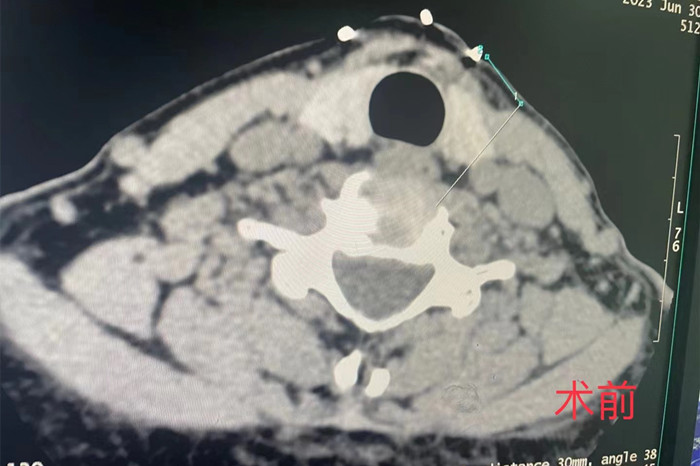

近日,我院疼痛科在南区影像科的配合下,成功开展了首例CT介导经皮穿刺颈椎间盘等离子射频髓核消融手术。

市民祁女士,今年51岁,近年来长期有头痛、颈肩部疼痛、僵硬和双上肢疼痛麻木不适等症状,辗转多家医院保守治疗均效果不佳,经我院疼痛科主任耿天勇对患者病史症状体征结合影像检查分析,诊断为颈椎间盘源性疼痛,遂决定在CT下为患者实施颈椎间盘射频消融的微创手术。

手术由安徽医科大学第一附属医院疼痛科主任王立奎和我院疼痛科副主任耿天勇共同主刀,在南区影像科医师的密切配合下,通过CT引导的精准定位,将细至0.9毫米的等离子射频针穿刺进入患者的病变椎间盘,成功对病灶部位进行射频消融,手术历时1小时左右。术后患者双上肢疼痛麻木即得到明显改善。